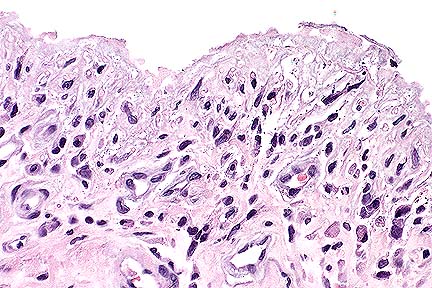

Ulceration and moderate subacute submucosal inflammation in the trachea of a dog with toxic epidermal necrolysis. (HE, 200X, 63K)

Loss of tracheal mucosal epithelium and a submucosal infiltrate of macrophages, lymphocytes, plasma cells and rare neutrophils in a dog with toxic epidermal necrolysis. (HE, 400X, 60K)

Contributor's Diagnosis and Comments: Severe necrotizing tracheitis associated with toxic epidermal necrolysis.

Toxic epidermal necrolysis (TEN) is a life-threatening, ulcerative skin disease that occurs rarely in the dog and cat. The facial skin, mucocutaneous junctions and oral mucosa are commonly involved. Necrosis of the mucosa of the trachea, large bronchi, pharynx and esophagus can also occur (Gross et al, 1992). Drug hypersensitivity reactions, neoplasia and concurrent infections have been implicated in the pathogenesis, although many cases are idiopathic. In TEN, early full-thickness epidermal necrosis occurs with minimal inflammatory reaction. Leukocyte infiltration occurs following ulceration. In this case, the ulcerative skin disease was advanced, with marked secondary pyoderma in areas of ulceration. This dog had no known exposure to drugs commonly associated with TEN, nor was there evidence of underlying infectious disease on postmortem examination.

AFIP Diagnosis: Trachea: Tracheitis, ulcerative, subacute, focally-extensive, severe, with pseudomembrane and squamous metaplasia, Pomeranian, canine.

Conference Note: Toxic epidermal necrolysis has been associated with drug therapy, systemic neoplasia, host vs. graft reactions, and bacterial infection. The pathogenesis is unknown. It is believed that cell-mediated immune mechanisms destroy the epidermal basal cells. Direct immunofluorescence in two cases of drug-induced TEN revealed intercellular fixation of immunoglobulins and complement in the basal cell layer of the epidermis.

Histologically, TEN is characterized by coagulative necrosis of the epidermis with minimal dermal inflammatory infiltrates. The necrotic epidermis separates from the dermis to form variably sized vesicles, which rupture, forming ulcers. Ulceration often induces a secondary dermatitis with predominance of neutrophils. Ultrastructural studies show condensation of tonofilaments around pyknotic nuclei and the disapperance of all organelles within the affected epithelial cells.